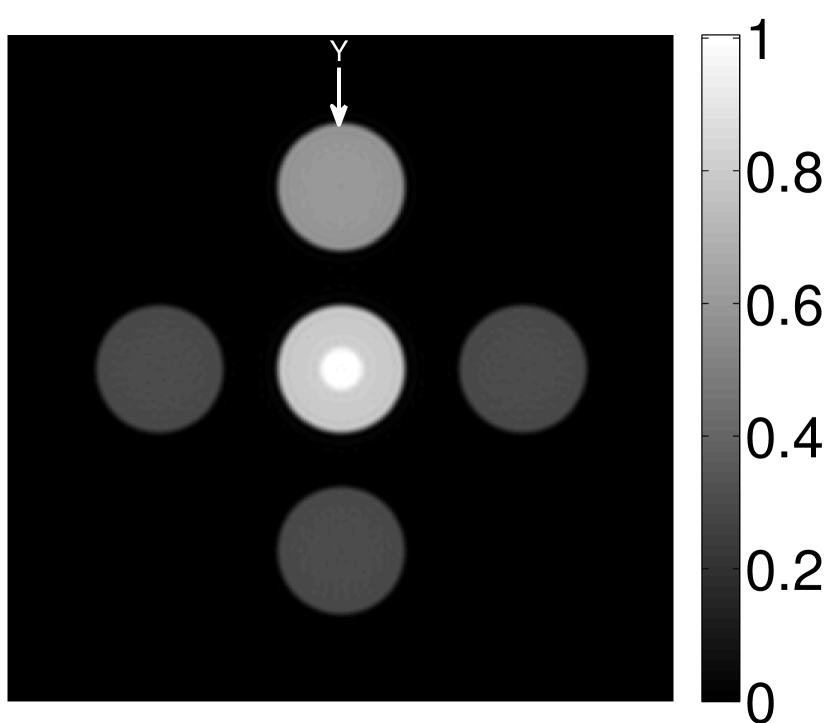

The numerical phantom shown in Figure 1(a) was employed. The phantom had a support area of mm2 and contained six uniform disks that were assigned different values of absorbed optical energy density.

A 2D circular measurement geometry was employed. transducers were evenly distributed on a ring of radius mm that enclosed the phantom. The SOS was assumed to be constant and set at mm/s. Since the simulated data were formed by use of the C-D imaging model in Eqn. (2), no inverse crime was committed. The components of this vector corresponded to equally spaced temporal samples over the interval s. Subsequently, the noiseless voltage vector was obtained by convolving the pressure data with EIR-1 in Figure 1(b).

The reconstruction region ( mm2) was represented by pixels with pixel size mm in each dimension. The initial guess of the EIR employed in the VP algorithm was different than the EIR that was assumed when generating the simulated data. This served to simulate a situation in which an experimentally measured EIR contained errors.

Each element in a real-world transducer array possesses its own EIR. In practice, the differences between the EIRs are sometimes neglected and an EIR corresponding to a single element may be used to represent all elements in the array. In some of the studies below, the EIR employed to initialize the VP algorithm (EIR-2 in Figure 1(b)) and the EIR employed to produce the simulated measurements (EIR-1 in Figure 1(b)) were experimentally measured from two different transducer elements in a circular transducer array (see Sec. VI-B). EIR-1 was measured by temporally integrating the PA signal produced by a point source positioned at the focus of the transducer. EIR-2 was measured by use of the method reported in [RNR2011]. In order to investigate the sensitivity of the VP algorithm to the initialization of the EIR, we employed different EIRs obtained by degrading EIR-1 as described later. When solving the sub-problem in Line-2 of Algorithm 1, was initialized as the zero vector. Algorithm 1 was terminated after 500 iterations, since it was observed that the changes in the reconstructed images with more iterations were negligible. When implemented by use of a single core of an Intel Xeon E5-2640 CPU, each iteration required approximately 7s to complete.